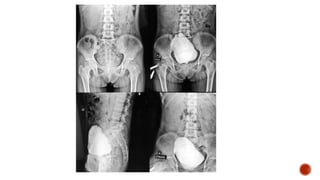

 Plain film :

 causes of stricture-

 pelvic trauma(pelvic bone fractrues)

 spinal cord injury(lumbar spine fracture)

 prostatic carcinoma mets to bones(stricture at prostatic level)

 Anterior :

 penile

 bulbar

 Posterior :

 membranous

 prostatic

 Verumontanem

 Bulbomembranous junction at the level of the inferior margin of the obturator

foramen